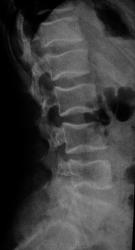

Ребенок 8 лет поступил в детское травматологическое отделение с болями в спине. На мой взгляд позвонки не нормальные. Изменены по типу рыбьих. может это вариант нормы или какая то система. Дистрофический процесс? Какие ваши мнения. и при каких состояниях, если это патология, мы можем видеть данные изменения. Буду рад полезным ссылкам)

прошу прощенья. ребенку 14 лет.

Рыбьи позвонки описывает Майкова-Строганова как результат остеопоротических изменений.(Кости и суставы в рентгеновском изображении. Туловище). БМЭ и Рейнберг такие позвонки относят к врожденным деформациям.

И еще:"Рыбьи позвонки — позвонки с двояковогнутыми краниальной и каудальной пластинками. Характерны для несовершенного остеогенеза, некоторых эндокринных спондилопатий, гемобластозов, хронического отравления солями тяжелых металлов." Э.В. Ульрих, А.Ю.Мушкин. Вертебрология в терминах, цифрах и рисунках, Спб, 2005

На счет "выпирания"дисков для меня сомнительно. При ф-х пробах все ок. Про смещения позвонков тоже недостоверно-смещение должно быть смещением(для меня). Про spina bifida - вполне согласен. Про анамнез уточню в понедельник, также про спорт и тд. Но мой главный вопрос - это двояковогнутые позвонки - норма или нет . и где предел нормы. За мнения спасибо.

И еще раскопала у себя книгу "Гормональная спондилопатия", авторы Герман и Кетрарь. При этой патологии формируются сначала "рыбьи позвонки", затем остеопроз приводит к патологическим переломам. Плюс куча всякой сопутствующей гадости. И отдельно выделена гиперпаратиреоидная дистрофия- болезнь Реклингаузена.

Если это ребенок, то скорее всего рыбьи позвонки результат дисплазии

Нормальным может быть "слегка вогнутая" поверхность тел позвонков в боковой проекции. Но не "столь вогнутая", как в данном случае. Тем более, что к 14 годам все уже почти как у взрослых. Вывод однозначен - не норма.